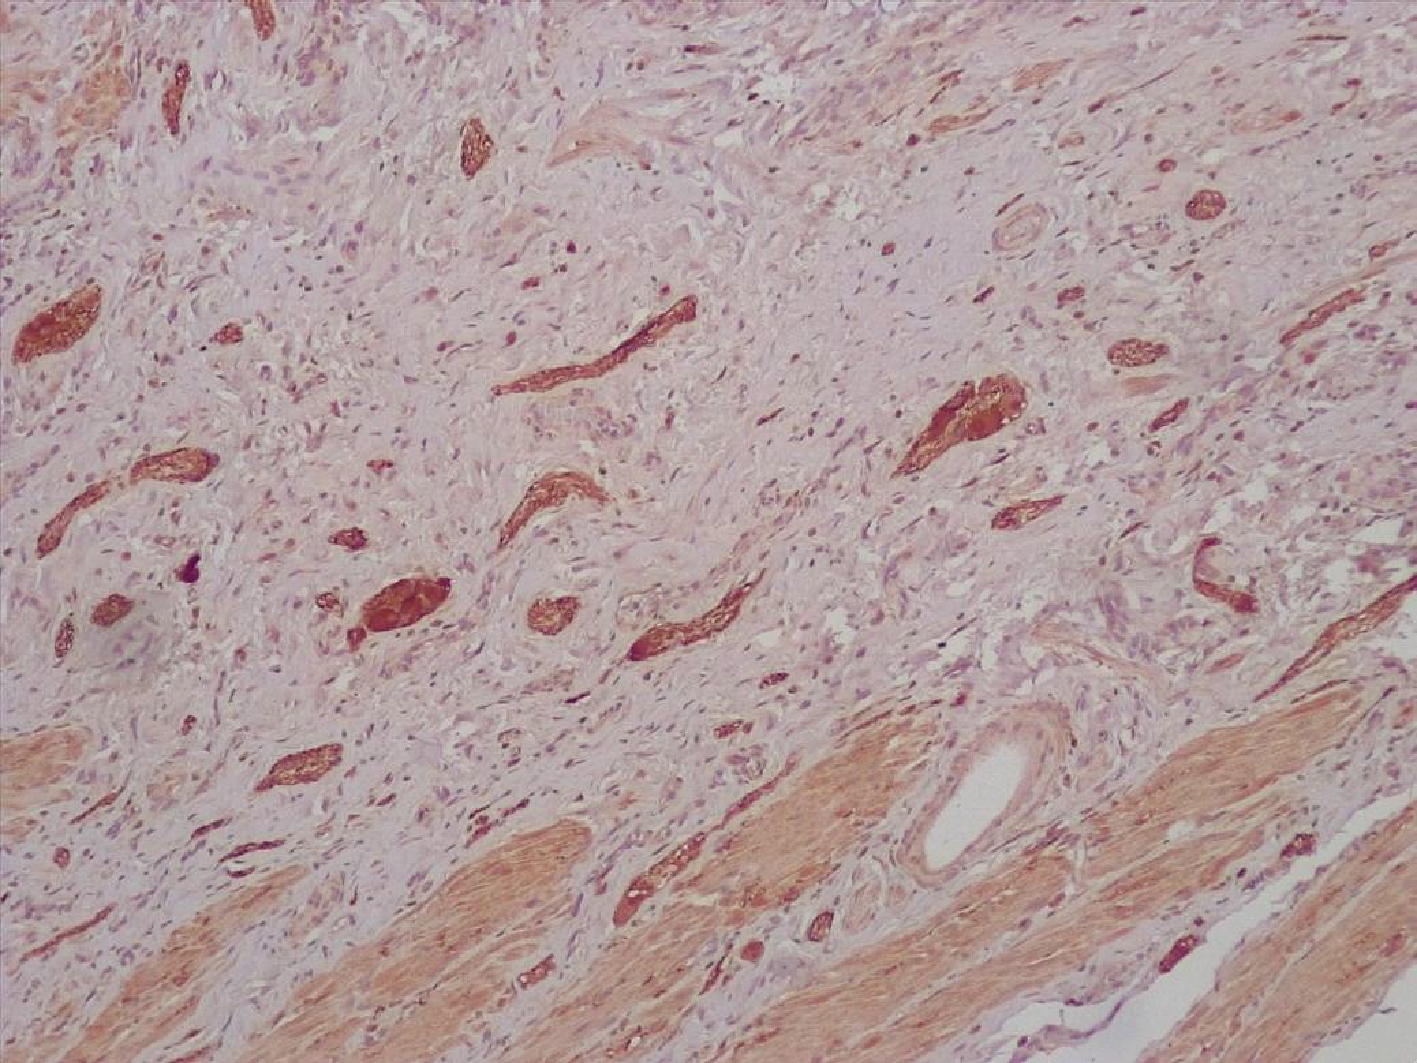

Строма вокруг опухоли была представлена рыхлой волокнистой соединительной тканью с признаками миксоматоза, с немногочисленными тонкими коллагеновыми волокнами, с экспрессией виментина (рис.3).

Рис.3. Строма аденокарциномы тонкой кишки с нейроэндокринным компонентом представлена немногочисленными тонкими коллагеновыми волокнами. Иммуногистохимическое исследование с антителами к виментину. Увеличение Х200.